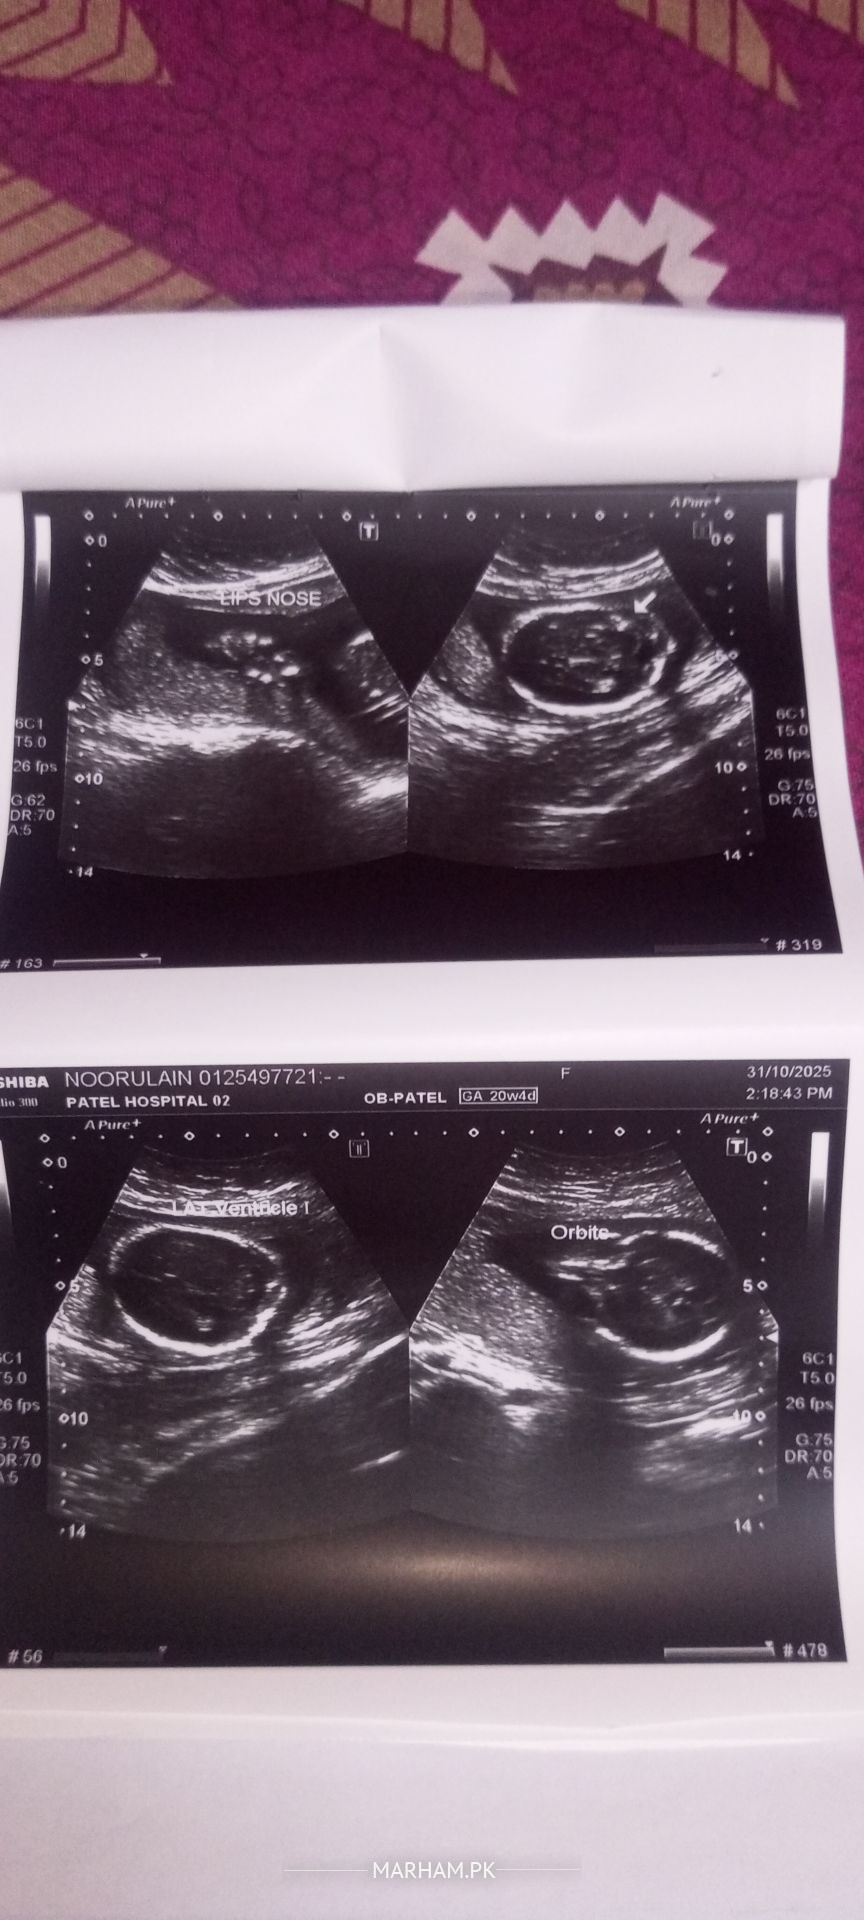

Attached in the anomaly scan report, I would request gynecologists to please comment Could I know baby's gender?

Salam Alaikum overall anomaly scan is normal but there is accumulation of urine in kidneys of fetus ,concern you gynaecologist need proper follow up.

Would it be resolved at later stages (weeks)?

It can resolve later in pregnancy you need serial ultrasound monitoring for this condition .